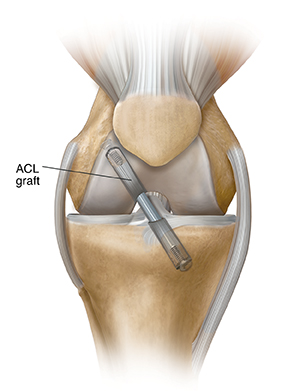

ACL tears

A torn ACL (anterior cruciate ligament) can make the knee unstable. You may have pain and swelling, and your knee may give out. Your surgeon can repair the ACL by reconstructing it. To rebuild your ACL, damaged tissue may be replaced with a graft of healthy tissue from an area near your knee, or from a donor.

| To replace damaged ACL tissue, a graft of strong, healthy tissue is attached. |